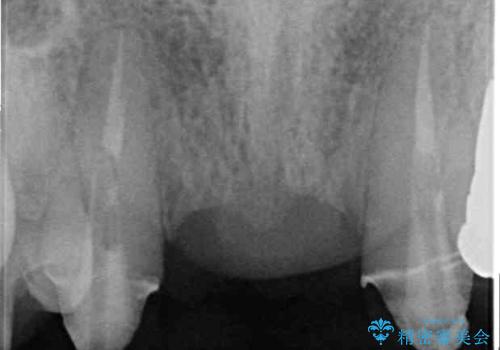

- 矯正治療を行った歯科医院で装着した前歯の仮歯が不快とのことで来院された患者様です。

仮歯自体はとても綺麗でしたが、2本の歯が欠損している部分に上唇小帯が入り込んでいたため、歯肉形成を行った上で仮歯を調整し、オールセラミックブリッジを装着することとしました。

上唇小帯を切除したことで、ブリッジのダミー部分に触れて腫れていた歯肉は健全な状態になりました。